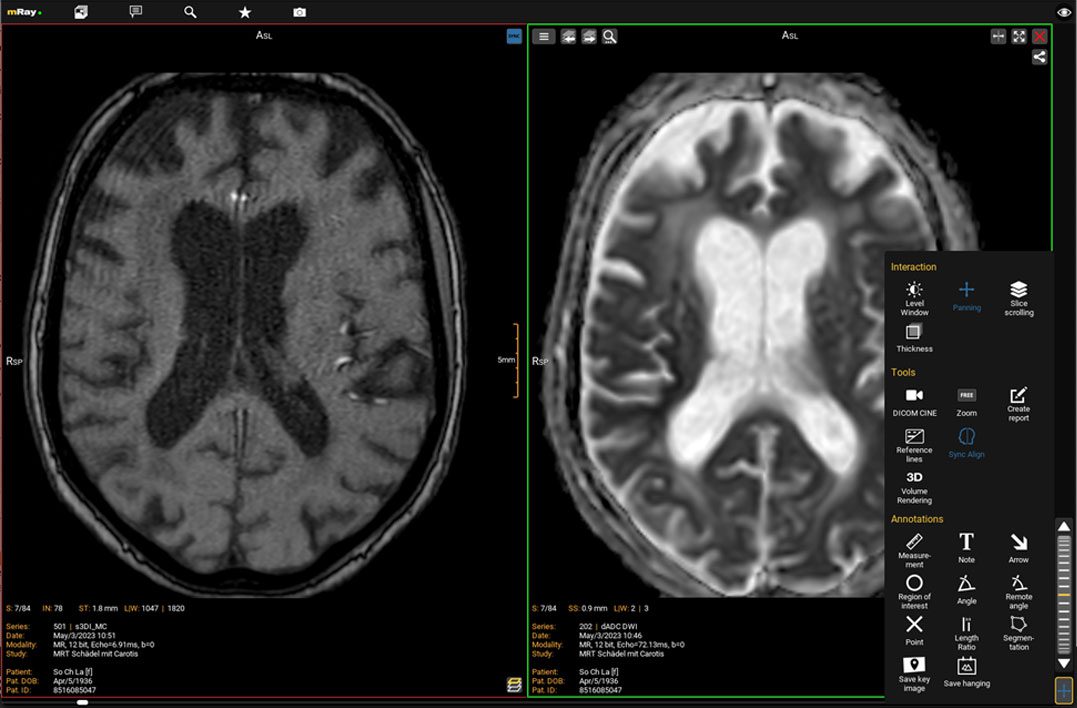

Synchronisierter Bildvergleich

Die neue Funktion ermöglicht es Ihnen, zwei oder mehrere Serien präziser zu vergleichen. Dabei werden sowohl die Ausrichtung als auch die Position der Bildebene synchronisiert.

Der „Sync-Align“ Button synchronisiert zwei Serien in ihrer Ausrichtung und Position